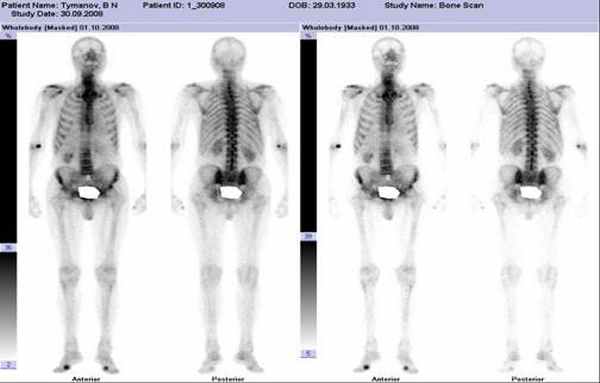

• Лучший критерий: замедление опорожнения желудка после приема и твердой пищи, и жидкости при динамической сцинтиграфии

(Справа) На КТ без контрастного усиления у мужчины 61 года, страдающего сахарным диабетом, визуализируется растянутый желудок, заполненный контрастным веществом и пищей, несмотря на то, что пациент не принимал пищу в течение 12 часов. Эти изменения означают задержку опорожнения желудка, возникшую в результате диабетического гастропареза. (Слева) При динамической сцинтиграфии, отражающей прохождение твердой пищи, меченой радиоактивным изотопом, у пациента с диабетическим гастропарезом, определяется умеренная задержка опорожнения желудка (опорожнение на 30% через 120 мин., на 55% через 240 мин.). Аналогичные изменения обнаружены и для жидкости.

(Справа) На скане, полученном при динамической сцинтиграфии желудка, определяется выраженная задержка опорожнения желудка при приеме твердой пищи (32% через 120 мин.). Пациент ранее перенес оперативные вмешательства, в т.ч. ваготомию и резекцию по Бильрот-2. Возникновению задержки опорожнения желудка у него, скорее всего, способствовал комплекс факторов.

Сцинтиграфия желудка с технецием является «золотым стандартом» диагностики нарушения МЭФ желудка. В 2000 г. был утвержден стандартизированный метод: при проведении сцинтиграфии пациент употребляет маркированную технецием пищу, в дальнейшем проводится измерение ее эвакуации из желудка каждые 15 мин в течение 4 ч. Прием препаратов, влияющих на МЭФ желудка, должен быть прекращен за 48–72 ч до исследования. Задержка более 60% пищи в желудке через 2 ч и более, 10% через 4 ч после приема пищи является диагностическим критерием нарушения МЭФ. Чувствительность метода составляет 93%, специфичность — 62% [31].